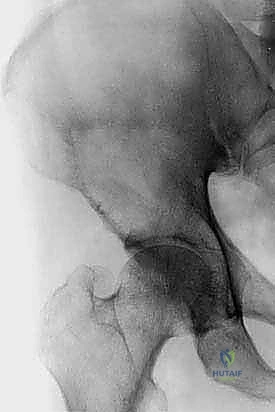

| الأشعة السينية (X-Rays) | الكشف الأولي عن تآكل العظام والكسور الكبيرة. | دقة متوسطة. تُظهر التلف فقط إذا فقد العظم 30-50% من كثافته. |

| التصوير المقطعي (CT Scan) | تقييم الهيكل العظمي بدقة ثلاثية الأبعاد. | دقة عالية جداً. أساسي للتخطيط الجراحي وقياس حجم التآكل العظمي. |